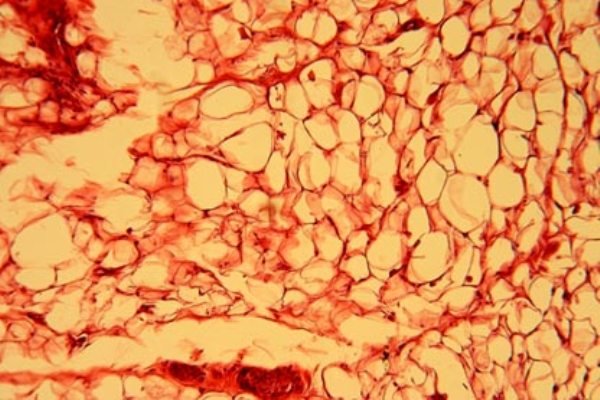

نوع غیرسالم چربی که با دیابت و اضافه وزن در ارتباط است تحت عنوان «چربی سفید» شناخته می شود که ترکیبی از بافت های بزرگ سلولی دربرگیرنده مقادیر هنگفتی انرژی است. اما چربی های «خوب» نیز وجود دارند.

آنچه که تحت عنوان چربی خوب از آن یاد می شود، بافت چربی قهوه ای رنگی است – سلولهایی که کوچکتر هستند و میتوکندری موجود در آنها چربی را سریعا به انرژی تبدیل می کند.